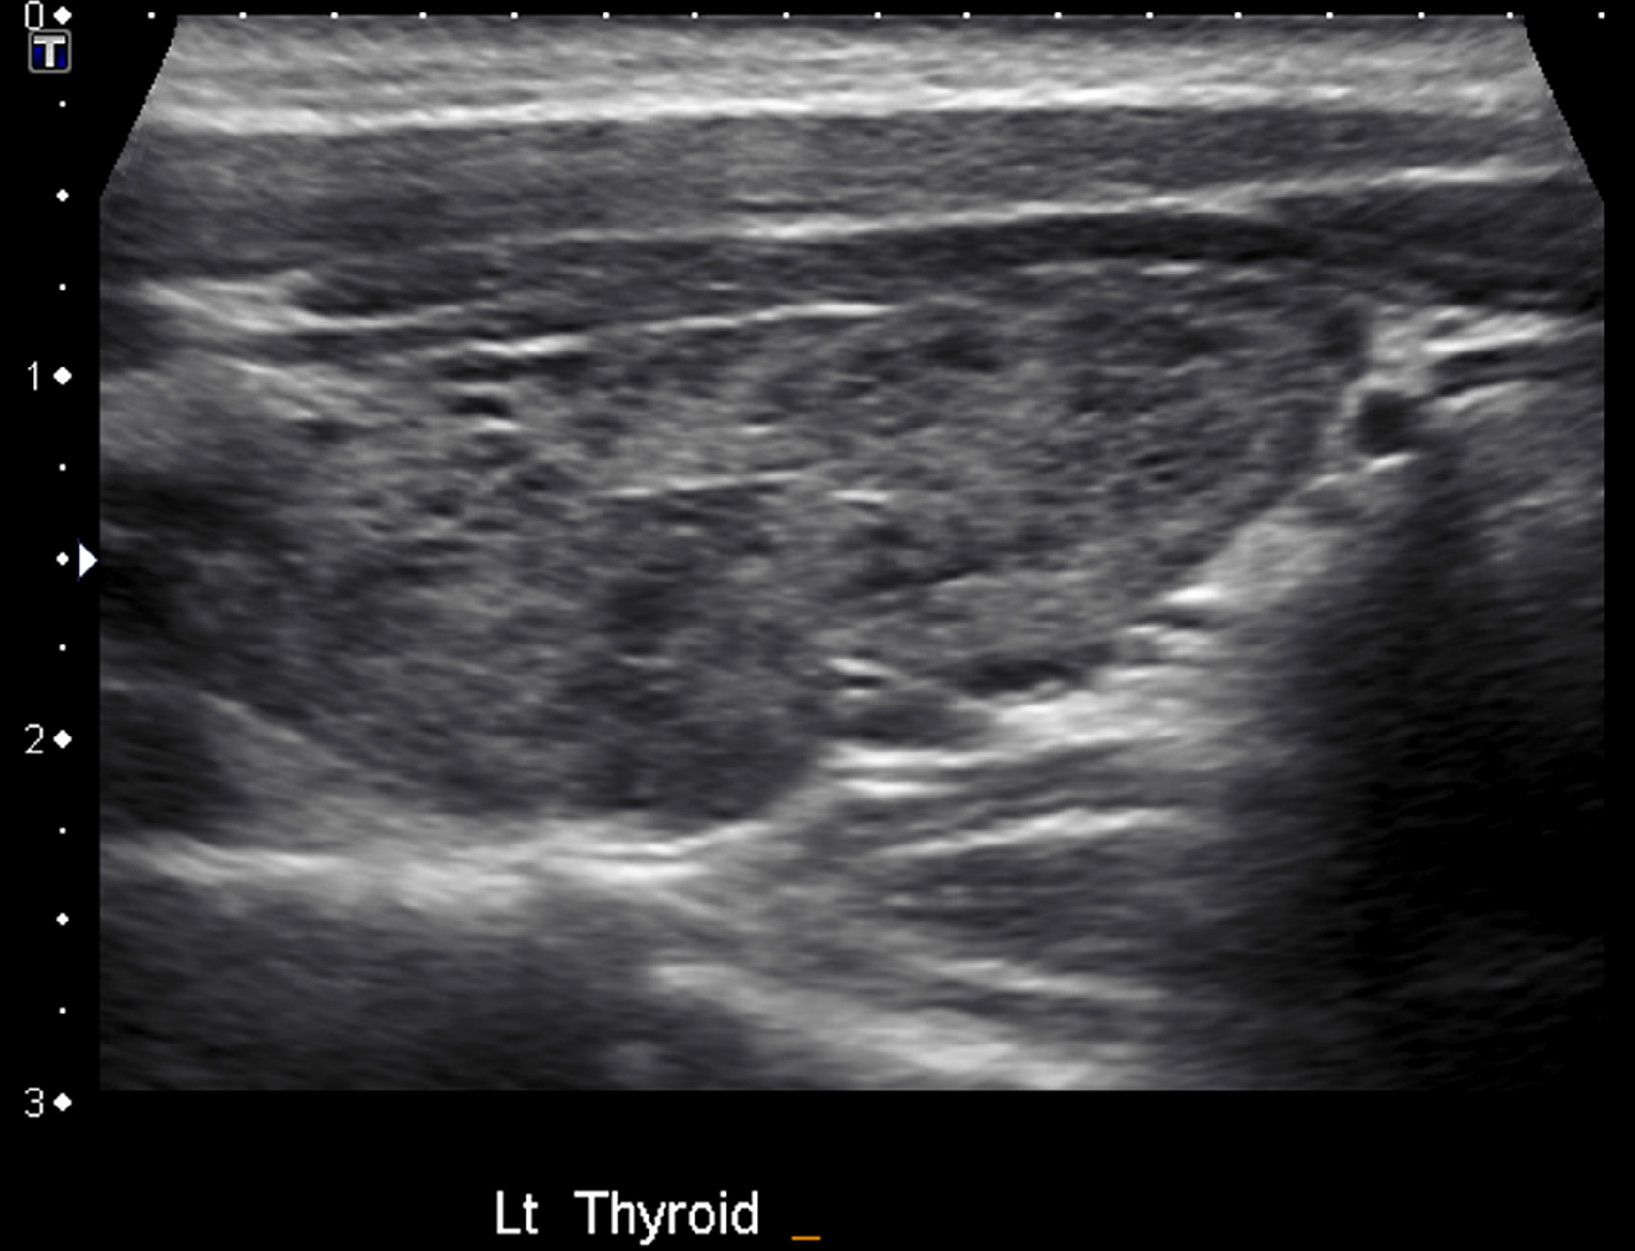

Radiology Hashimoto's Thyroiditis . a micronodular pattern on ultrasound is highly diagnostic of hashimoto thyroiditis with a positive predictive value of 95% [ 2 ]. This autoimmune disease of the thyroid gland is the most common. The purpose of this article is to analyze the sonographic appearance of nodular hashimoto thyroiditis. hashimoto’s thyroiditis (ht), also known as chronic lymphocytic thyroiditis (clt) or autoimmune thyroiditis. Ht 1 (also known as chronic lymphocytic thyroiditis or autoimmune thyroiditis) is.